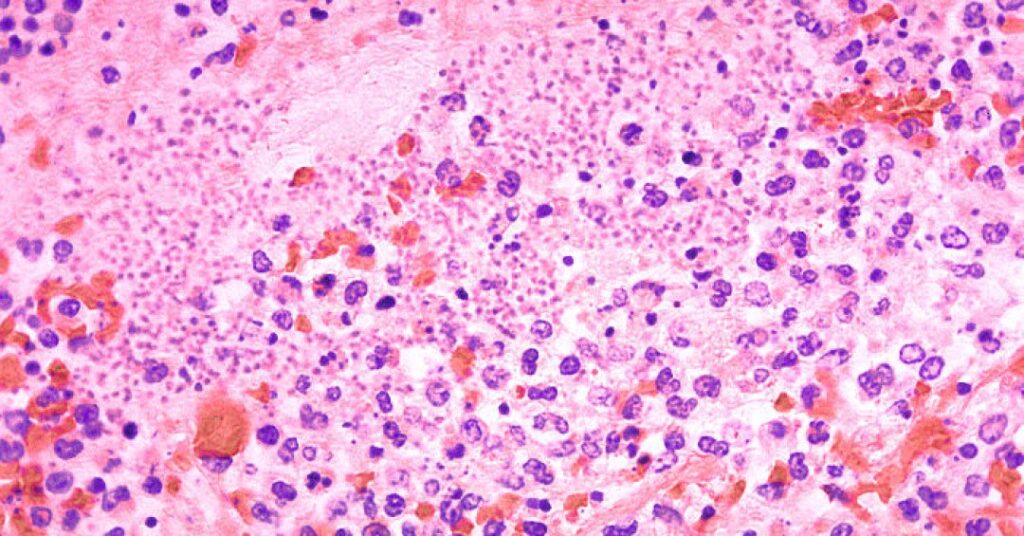

A peste pneumônica é um dos tipos de infecção possíveis pela Yersinia pestis, bactéria famosa pela peste bubônica, que matou milhões de pessoas na Europa durante a Idade Média.

Como o nome sugere, a versão pneumônica da doença acomete os pulmões. Ela é a mais rara, mas também é considerada a mais letal das doenças causadas por essa bactéria, levando a uma pneumonia grave que, com frequência, culmina em falência respiratória.

Todos os tipos de peste são causados pela bactéria Yersinia pestis. De modo geral, as principais diferenças entre a peste pneumônica e a bubônica dizem respeito à parte do corpo acometida pela infecção e ao modo de contágio.

A peste bubônica é caracterizada pela infecção e inchaço dos linfonodos, enquanto a pneumônica ataca os pulmões. Muito mais comum (e com mais chance de sobrevivência), a bubônica é causada pela mordida de pulgas infectadas pela bactéria. Já a pneumônica costuma ocorrer pela inalação de gotículas de saliva ou respiratórias vindas de um animal ou de uma pessoa infectada.

Além da bubônica e da pneumônica, também existe a peste septicêmica, que ocorre quando a Yersinia pestis entra na corrente sanguínea, seja pela mordida das pulgas ou pelo contato de ferimentos abertos com fluidos de animais infectados. Sem tratamento, essa versão pode causar gangrenas e falência de órgãos internos.